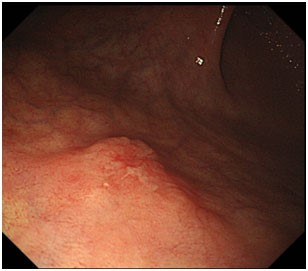

Erken teşhis konulmasına bir diğer önemli uygulama boyama yöntemidir. Bu yöntemde mide içeriği tümü ile aspire edilip yıkandıktan sonra, mide mukoazası özel boyalarla boyanır. Kanser hücreleri boyayı az tutar. Halbuki normal mide mukozası hücreleri homojen şekilde boyanır. Bu durum işlem sırasında boyayı az tutan kanser hücrelerinin tanınmasını sağlar. Kanser hücrelerinin diğer bir özelliği de boyama sonrası yıkama yapıldığında, tuttuğu boyayı bırakmaz. Normal mide mukoza hücreleri ise boyama sonrası yıkama yapıldığında boya maddesini tümü ile bırakır ve homojen bir görüntü verir. Bu özellik de yine kanser hücrelerinin tanınmasını kolaylaştırıcı önemli bir faktördür. Sonuç olarak boyama yöntemi kanser hücrelerini endoskopi işlemi sırasında tanınır hale getirir, biyopsi alınarak ve tanı konulmasını sağlar.

Biz yaptığımız endoskopik incelemelerde, muayene öncesinde mutlaka hastada geniş bir sorgulama yapmaktayız ve eğer varsa risk faktörlerini ortaya koymaktayız. Riskli grupdaki hastalara ve mide kanseri alarm semptomlarına sahip olan hastalarımızda mutlaka boyama tekniğini kullanıyoruz. Bu şekilde mide kanserini erken evrede yakalamak mümkün olmaktadır. Erken evrede yakaladığımız mide kanseri hastalarımızı çok büyük cerrahi ameliyatlara gerek kalmadan endoskopik submukozal diseksiyon tekniği ile tedavi etmekteyiz. Boyama öncesi ve sonrası elde edilen bazı görüntüler aşağıda sunulmuştur.